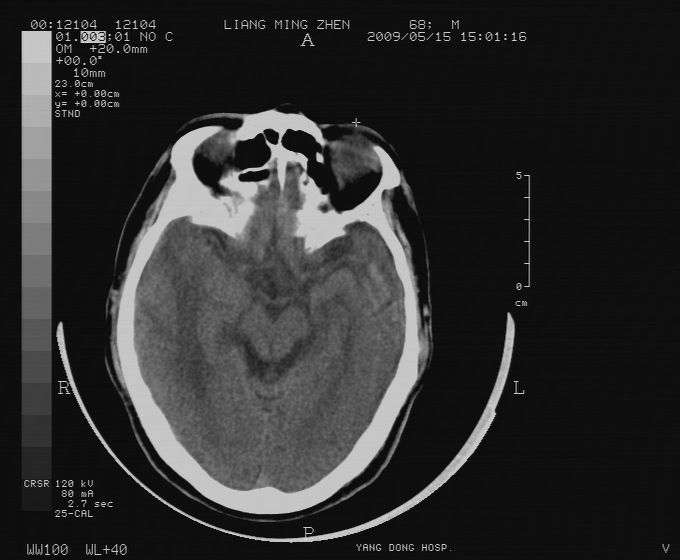

标题: CT19966:男性,六十岁,有高血压及鼻咽癌病史,头晕,呕吐 [打印本页]

双侧颞叶均见一高密度结节影,周围有水肿。结合病史,考虑转移瘤并出血可能性大。

这个病例很好 右颞部可见类圆形稍高密度影,边界还是很清楚,结合病史还是考虑转移可能并出血;

结节+很大的水肿+病史=转移

考虑放射性脑病,合并出血可能

可考虑右颞叶区脑出血、瘤体出血、脑膜瘤等,建议增强扫描或mri检查助诊。